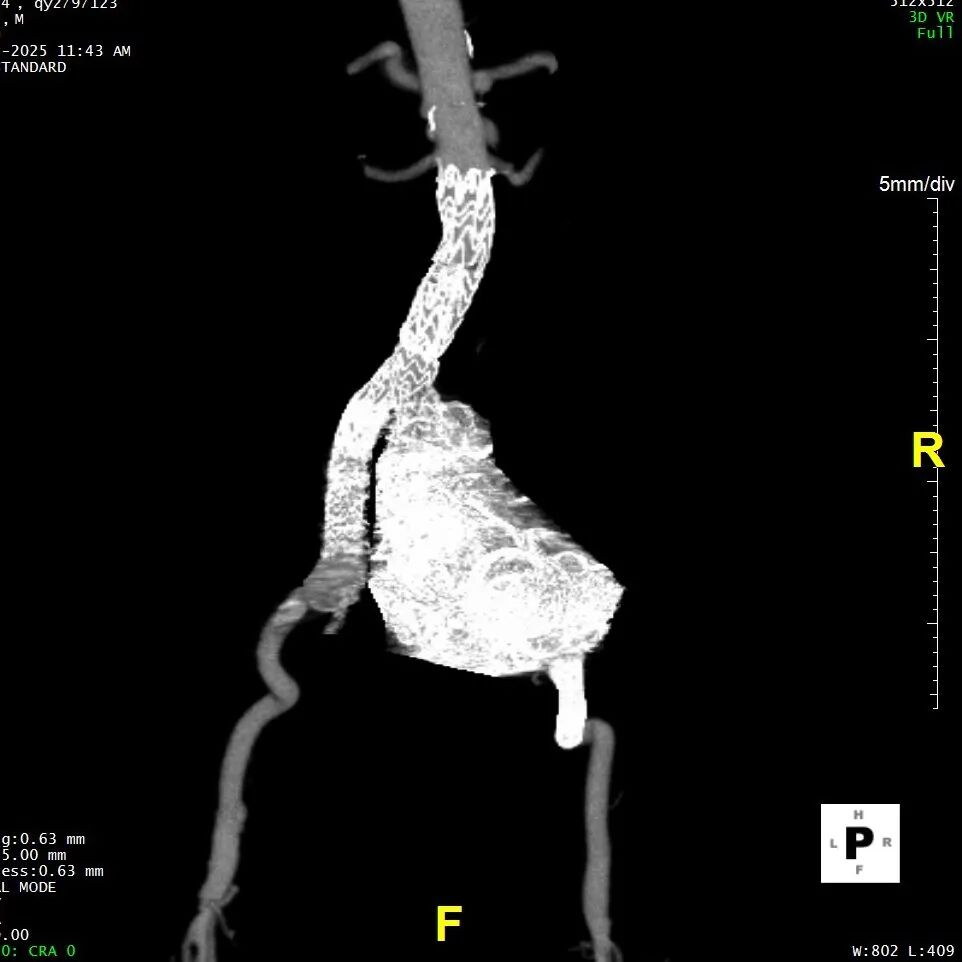

现病史:患者7小时前无明显诱因出现腹部胀痛不适,以下腹部为主,无发热、恶心、呕吐,无头晕、头痛等特殊不适,因症状持续不缓解,遂来我院急诊就诊,行腹主动脉(下腹部、盆腔段)CTA示:腹主动脉下段,右侧髂总动脉动脉瘤形成,右侧巨大髂总动脉(直径85.0mm*77.1mm)有明显造影剂溢出提示破裂,腹主动脉周围、左侧肾周、左侧腰大肌前缘及骶前积血较前明显增多,于急诊抢救室出现一过性意识丧失、血压下降休克状态,予积极补液后症状好转,现为进一步治疗,急诊以“腹主动夹层动脉瘤;髂动脉巨大动脉瘤破裂”收入院。

二、术前CTA详解

gore医疗怎么样「漫腹精论」髂合时宜 精益求精——双MOB球囊导管辅助腹主动脉覆膜支架急诊治疗破裂巨大髂动脉瘤_https://www.jmylbn.com_新闻资讯_第5张

gore医疗怎么样「漫腹精论」髂合时宜 精益求精——双MOB球囊导管辅助腹主动脉覆膜支架急诊治疗破裂巨大髂动脉瘤_https://www.jmylbn.com_新闻资讯_第6张

gore医疗怎么样「漫腹精论」髂合时宜 精益求精——双MOB球囊导管辅助腹主动脉覆膜支架急诊治疗破裂巨大髂动脉瘤_https://www.jmylbn.com_新闻资讯_第7张

gore医疗怎么样「漫腹精论」髂合时宜 精益求精——双MOB球囊导管辅助腹主动脉覆膜支架急诊治疗破裂巨大髂动脉瘤_https://www.jmylbn.com_新闻资讯_第8张

gore医疗怎么样「漫腹精论」髂合时宜 精益求精——双MOB球囊导管辅助腹主动脉覆膜支架急诊治疗破裂巨大髂动脉瘤_https://www.jmylbn.com_新闻资讯_第9张

gore医疗怎么样「漫腹精论」髂合时宜 精益求精——双MOB球囊导管辅助腹主动脉覆膜支架急诊治疗破裂巨大髂动脉瘤_https://www.jmylbn.com_新闻资讯_第10张

gore医疗怎么样「漫腹精论」髂合时宜 精益求精——双MOB球囊导管辅助腹主动脉覆膜支架急诊治疗破裂巨大髂动脉瘤_https://www.jmylbn.com_新闻资讯_第11张

五、术后随访

患者术后进行随访,支架形态良好,瘤体隔绝良好,分支血管通畅,预后满意。